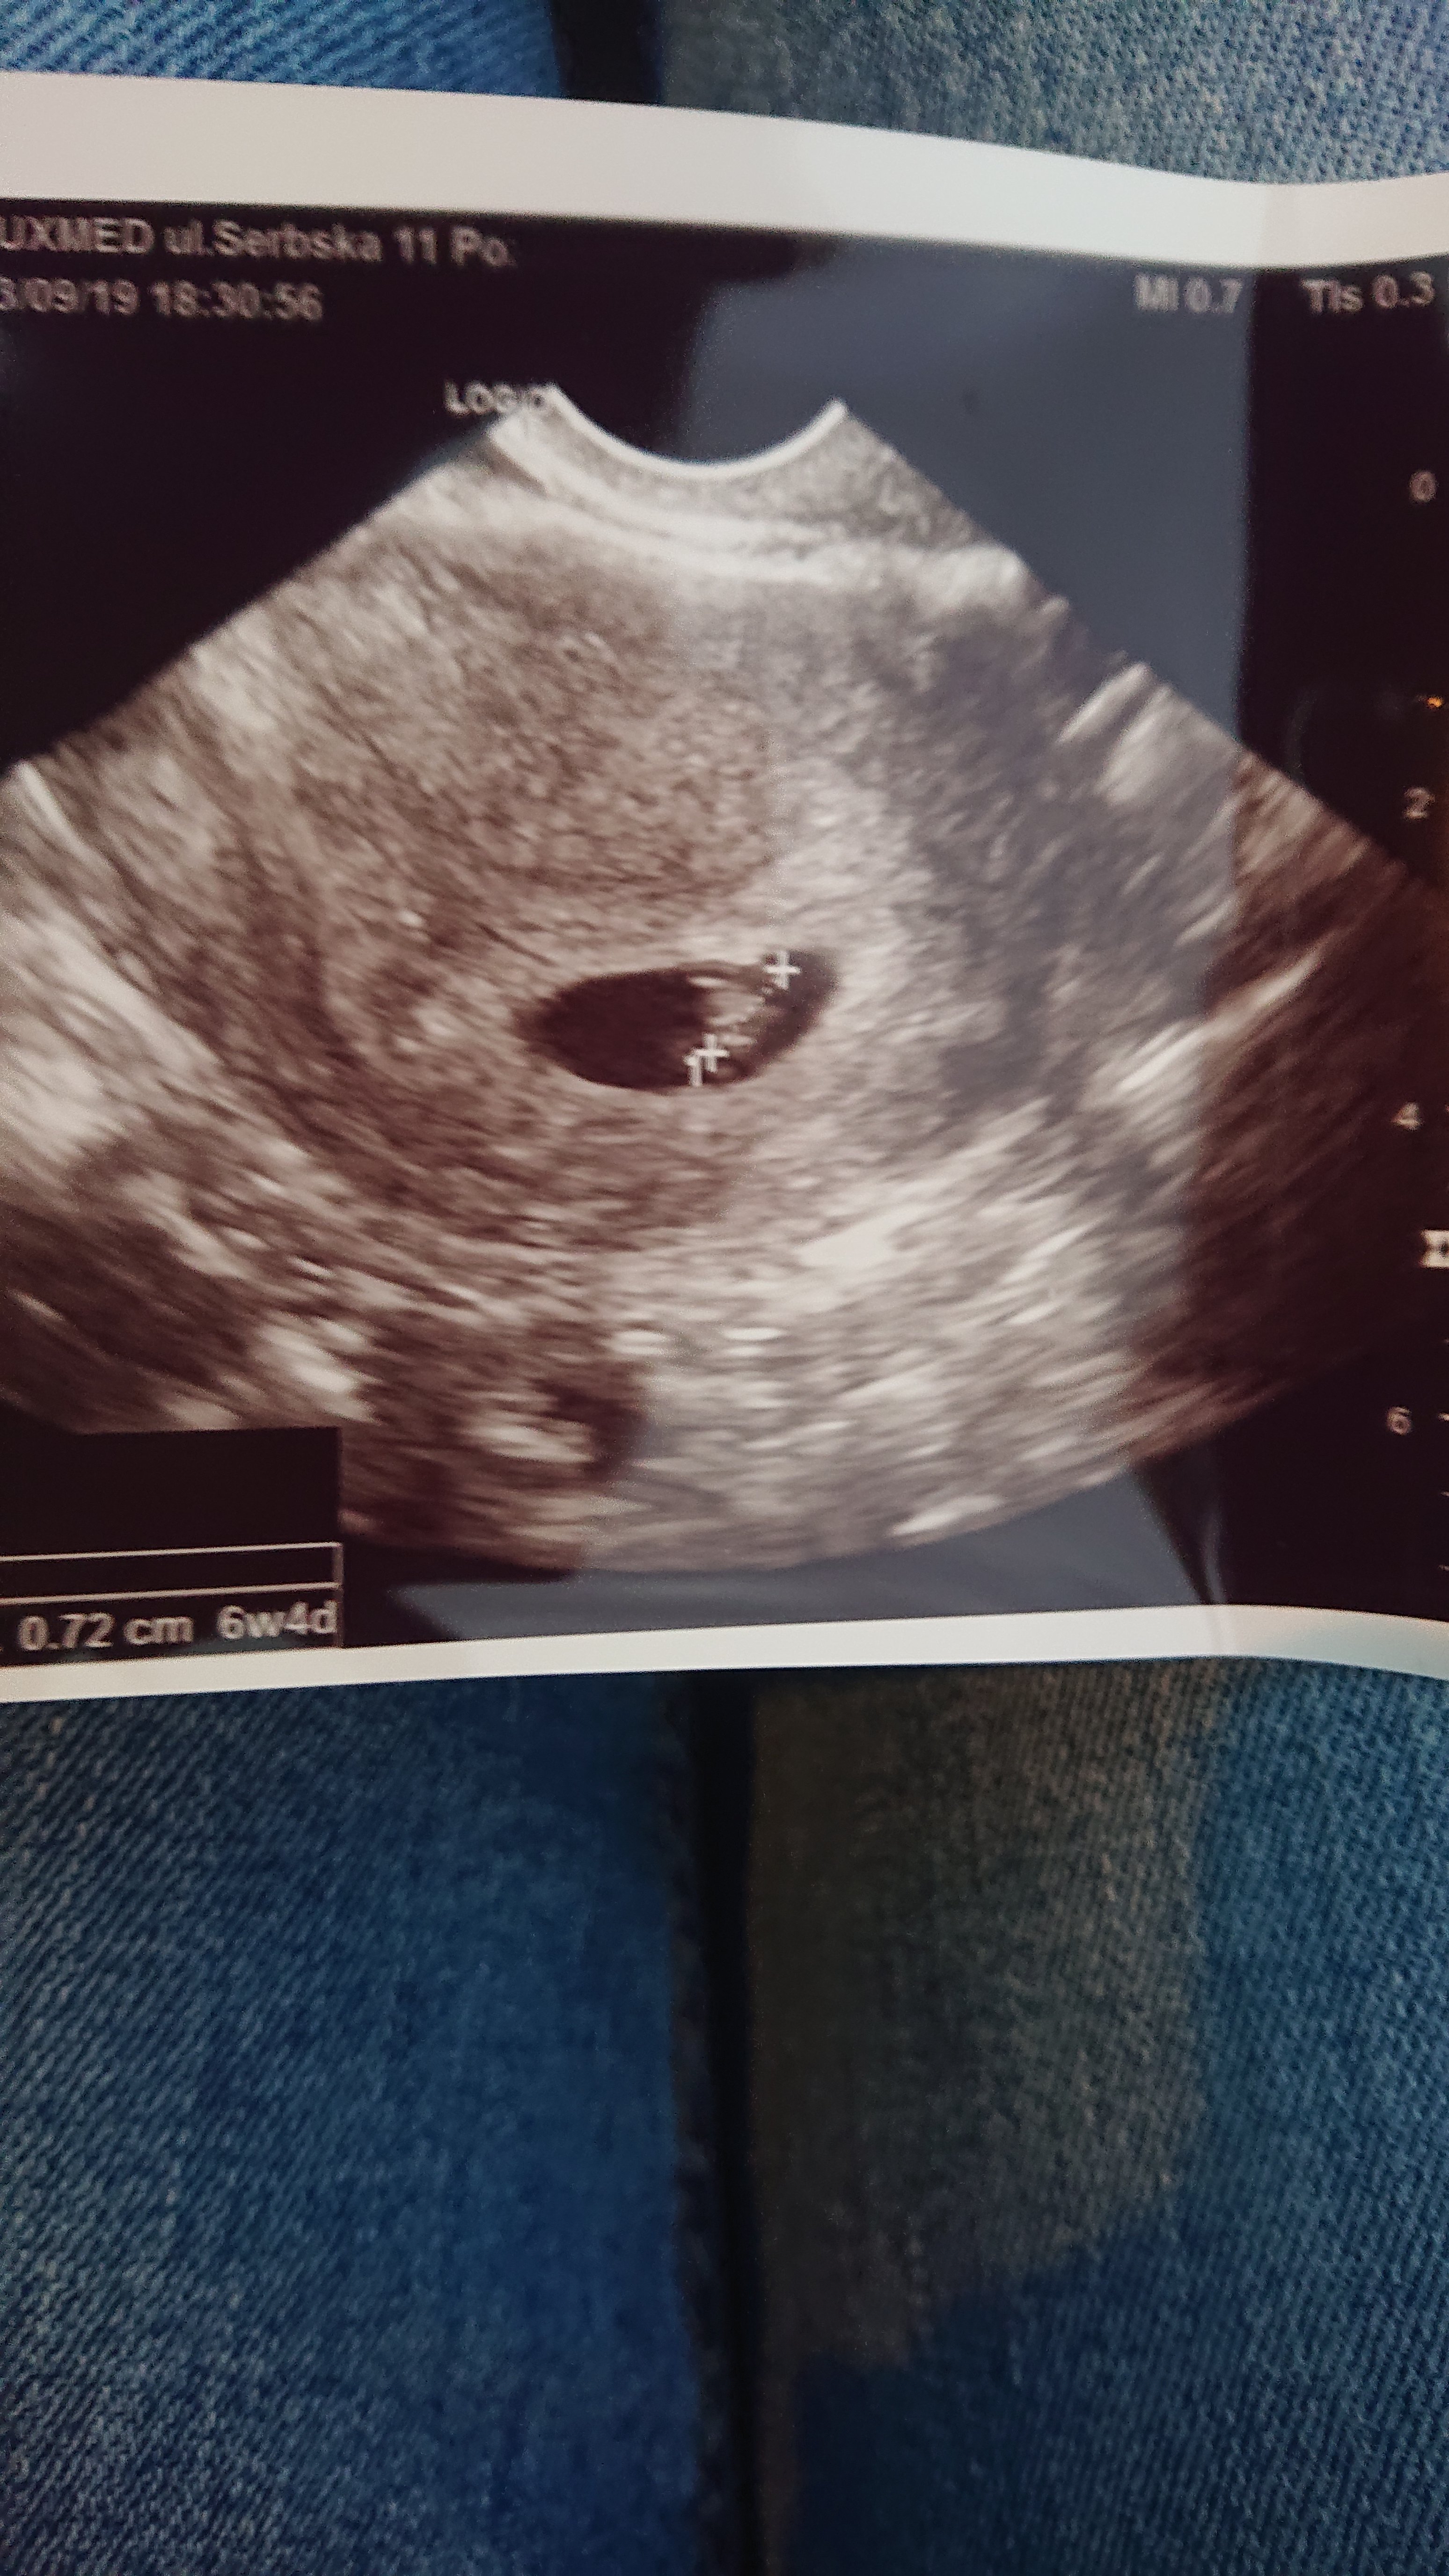

Tak :) Twoje też będzie podobnie wyglądać, jestem pewna. Tymczasowo zawieszam swoją aktywność na forum, bo za dużo sobie wciskam i się stresuję, ale wiem, że będzie dobrze!

Załączniki

• DSC_0275.JPG

DSC_0275.JPG

2 MB · Wyświetleń: 336